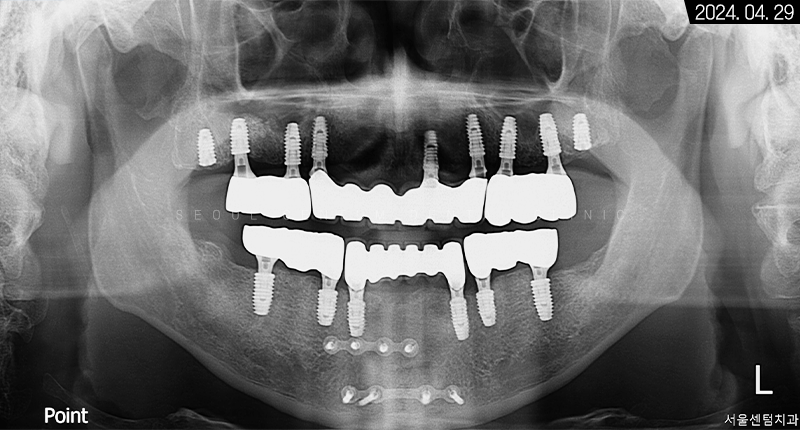

파노라마 엑스레이 사진을 보면 뿌리 주변이 골 소실로 인해 까맣다는 것을 확인할 수 있습니다.

3개월이 더 지난 후 치근단 사진과 파노라마 엑스레이 사진으로 살펴봐도 초기 임플란트 식립 상황과 동일하게 견고히 자리 잡아 있는 것을 볼 수 있었습니다. 주위염도 생기지 않아 이상적인 결과를 만들어볼 수 있었어요.